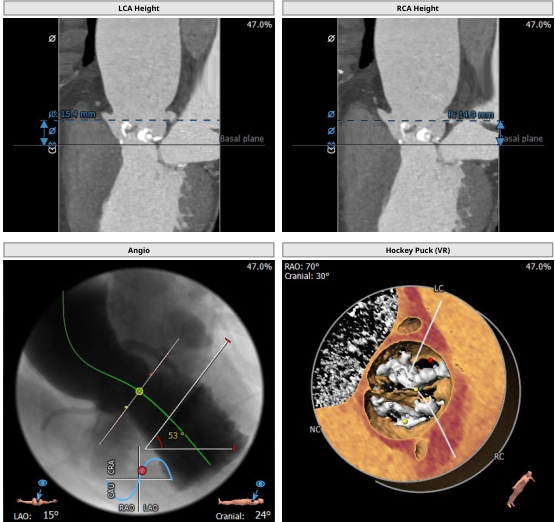

TYPE0型二叶式主动脉瓣,瓣叶严重钙化增厚。冠脉无明显狭窄,冠脉开口高度左侧15.4mm、右侧14.9mm,冠状窦水平无瓣叶,TAVR手术冠脉闭塞风险低。升主动脉扩张,主动脉扭曲。双侧股动脉通畅,无明显钙化。

二叶瓣严重钙化(如图A、B 所示术前CT检查及术中影像均可见明显钙化团块),术中发生瓣周漏、瓣膜移位、瓣环破裂等风险较高,TAVR操作具有一定挑战性。升主动脉明显增宽,再加上主动脉瓣钙化严重,为器械输送增加难度。

瓣膜选择:基于术前CTA的测量结果,因二叶瓣严重钙化为降低瓣环破裂等风险选择偏小一号的人工瓣膜(downsize策略)植入23 mm SAPIEN 3瓣膜。